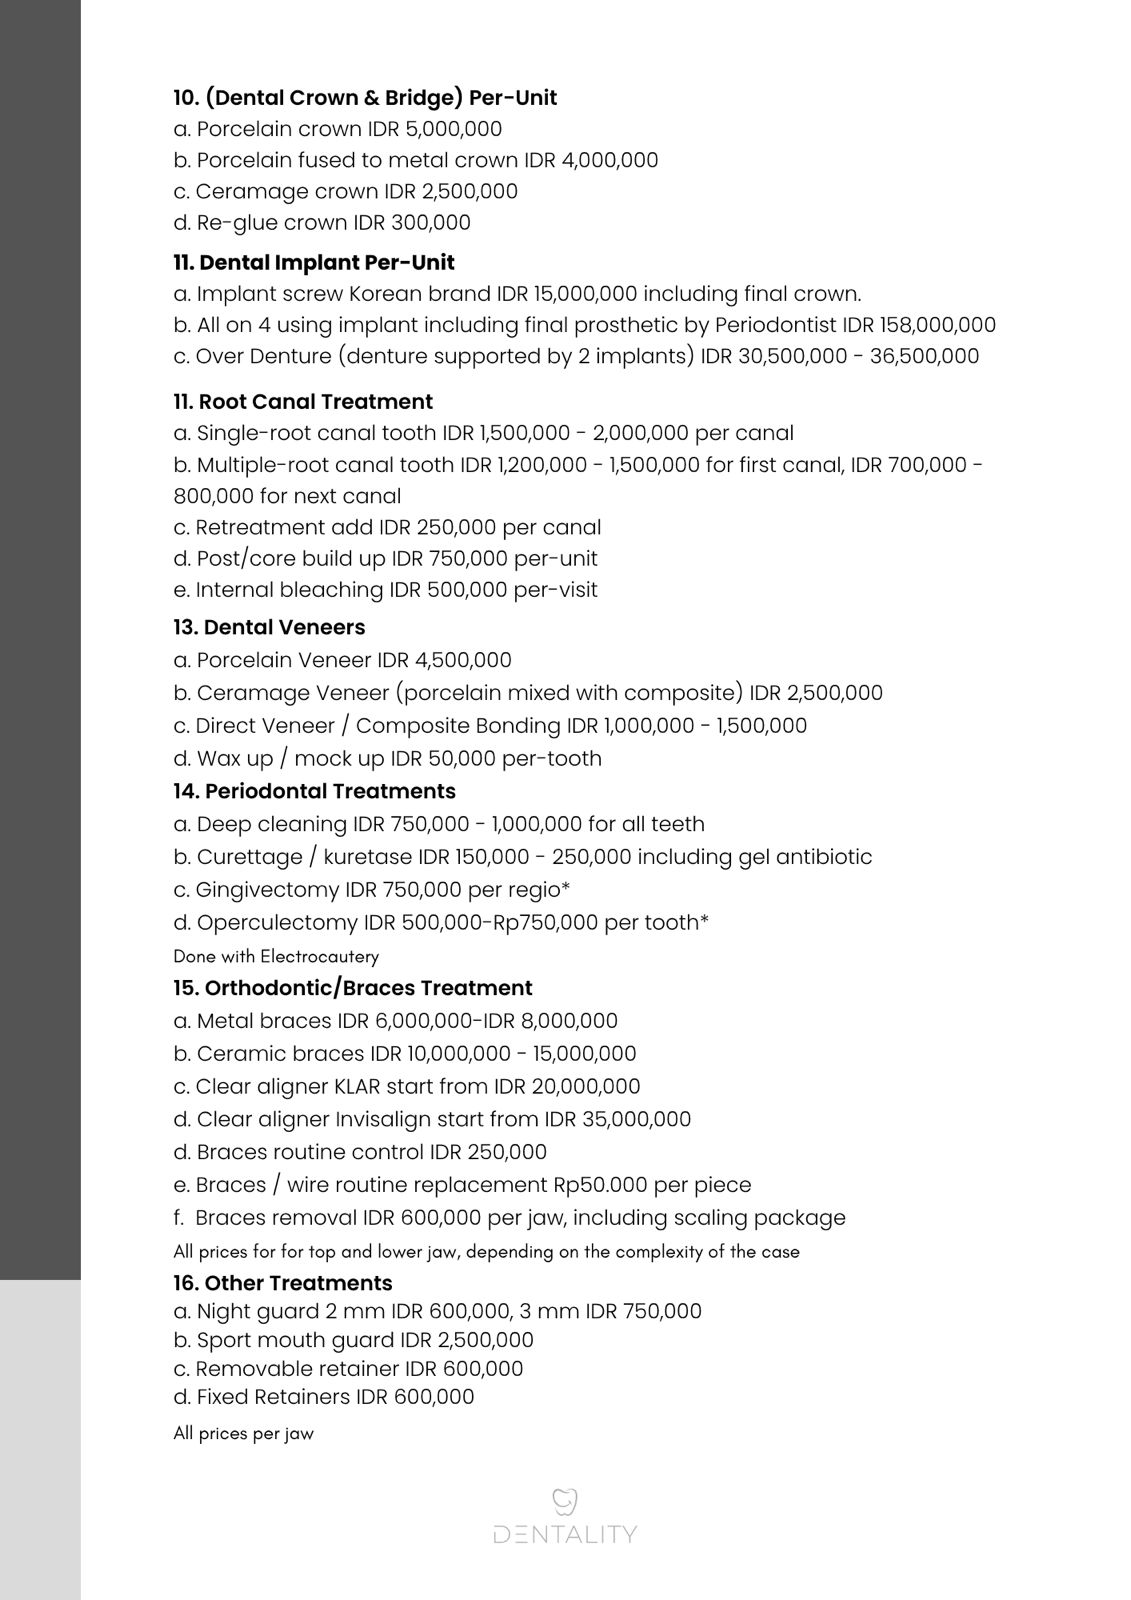

Semuanya, dari scaling, whitening, tambal gigi, hingga implant dan crown gigi.